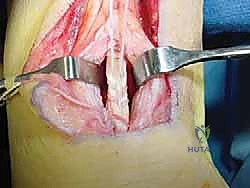

3. استئصال الأنسجة التالفة (Debridement)

هذه خطوة حاسمة. يتم فتح الغلاف المحيط بوتر أخيل وفحص الوتر بدقة. يقوم الجراح بإزالة جميع الأنسجة الندبية، الميتة، والمتكلسة (التي تسبب الألم). في الحالات الشديدة، قد يتم إزالة أكثر من 50% من حجم وتر أخيل الأصلي لأنه لم يعد صالحاً للعمل.

4. عزل وحصاد وتر FHL (Tendon Harvesting)

يتم تحديد مسار وتر FHL الذي يقع أعمق قليلاً من وتر أخيل. يتم فصل الوتر بعناية من نقطة اتصاله السفلية (عند منتصف القدم تقريباً) لضمان الحصول على طول كافٍ للنقل. وتجدر الإشارة هنا إلى أن قطع هذا الوتر لا يؤثر بشكل ملحوظ على وظيفة المشي أو حركة إصبع القدم الكبير، حيث تتولى عضلات أخرى هذه المهمة بكفاءة.